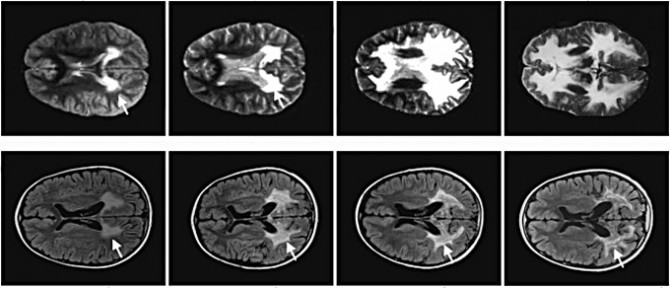

To assess whether genetically modified CD34+ cells could develop into cells of the immune system when injected into the bone marrow they selected the NOD/SCID mouse that lacks a functioning immune system and is often used to assess human stem cell transplantation techniques and to study aspects of the human immune system. Initial results with retroviral vectors were disappointing but using the NOD/SCID mouse model they developed a lentiviral vector based on HIV-1 that enables the functioning ABCD1 gene to safely incorporate into the genome of a significant proportion of the cells and drive ABCD1 expression in immune system cells derived from them (1). What is more they found that as well as the expected range of immune cells the genetically modified CD34+ cells migrated to the brain and differentiated into microglial cells (2). Of course if the therapy is to prevent disease progression the vector needs not only to drive expression of ABCD1 but to do so reliably for many years,. To assess whether the lentiviral vector could do this they transplanted Sca-1+ cells, the mouse equivalent of human CD34+ cells, containing the ABCD1 expressing lentiviral vector into mice that lacked a functional ABCD1 gene, and found that even 12 months after transplantation almost a quarter of microglial cells in the mouse brain expressed ABCD1 (3).